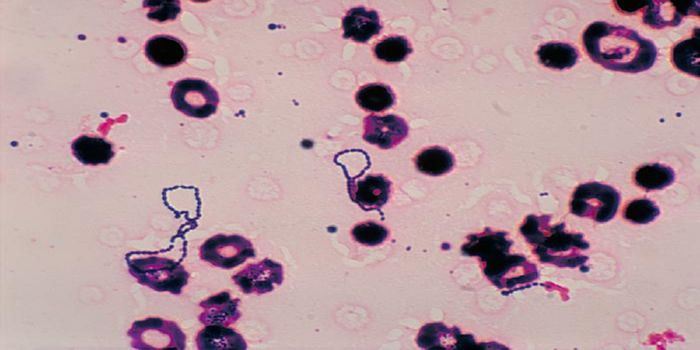

MAR 17, 2017Health & MedicineThe first human case of babesiosis was reported in 1957; until then it was thought of as a disease plaguing domes ...

OCT 27, 2017Clinical & Molecular DXMadagascar is currently battling a plague outbreak that has so far infected nearly 1,200 people and killed 124 people. I ...